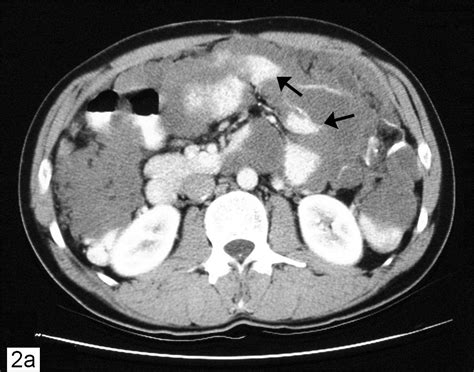

So, you’ve got some symptoms, and your doctor suspects something more is going on. Diagnosing pseudomyxoma peritonei involves a multi-pronged approach, and it can sometimes be a bit of a puzzle. Because the symptoms can be so non-specific, it often starts with a thorough medical history and physical examination. Your doctor will ask about your symptoms, their duration, and any relevant personal or family medical history. During the physical exam, they’ll likely check for abdominal distension, tenderness, or any masses. Imaging tests are absolutely crucial for getting a clearer picture. CT scans (Computed Tomography) are usually the first line of imaging. They can help visualize the extent of mucus accumulation within the abdomen and pinpoint potential primary tumor sites, like a suspicious appendix or ovarian mass. MRI (Magnetic Resonance Imaging) might also be used to provide more detailed images of soft tissues. Blood tests might be performed, but they typically don’t provide a definitive diagnosis for PMP itself. However, they can help assess overall health and rule out other conditions. The definitive diagnosis, however, usually requires a biopsy . This involves obtaining a tissue sample of the abdominal masses or the mucus itself. This can be done through a minimally invasive laparoscopic procedure or during surgery. Pathologists then examine the tissue under a microscope to confirm the presence of mucinous tumor cells and rule out other types of cancer. Sometimes, PMP is discovered incidentally during surgery for another condition, like an appendectomy for what was thought to be a routine appendicitis. The key takeaway here is that a combination of clinical suspicion, advanced imaging, and pathological confirmation is needed to accurately diagnose pseudomyxoma peritonei. It’s a process that requires careful evaluation by experienced medical professionals.